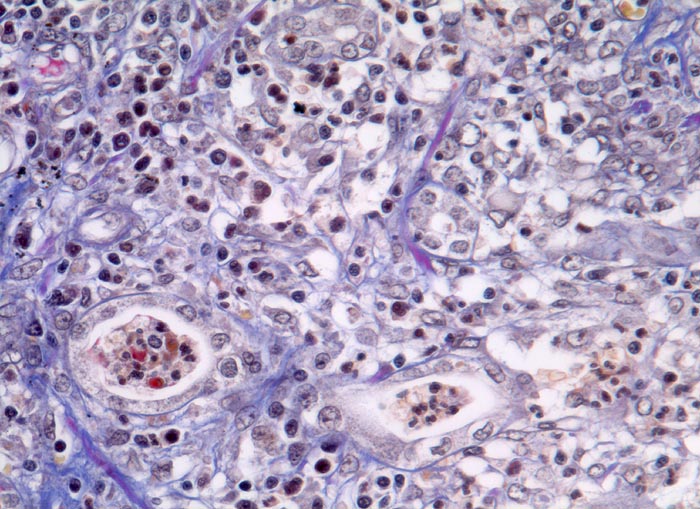

PathoPic – image database / PathoPic ID 5005 - extrakapilläre Glomerulonephritis bei Morbus Wegener

extrakapilläre Glomerulonephritis bei Morbus Wegener

Systemerkrankung/Immunpathologie

Niere

Lymphohistiozytäre und teils granulozytäre Entzündung im tubulointerstitiellen Raum mit ödematöser Gewebsauflockerung. Die Tubuli sind ausgekleidet von abgeflachtem Epithel und enthalten Fibrin, Zelldetritus und Granulozyten.

Rapid progressive Glomerulonephritis mit Entwicklung einer Oligurie innert weniger Tage. Fieber und Nachtschweiss. Chronische Sinusitis. cANCA erhöht.

Histologie

320